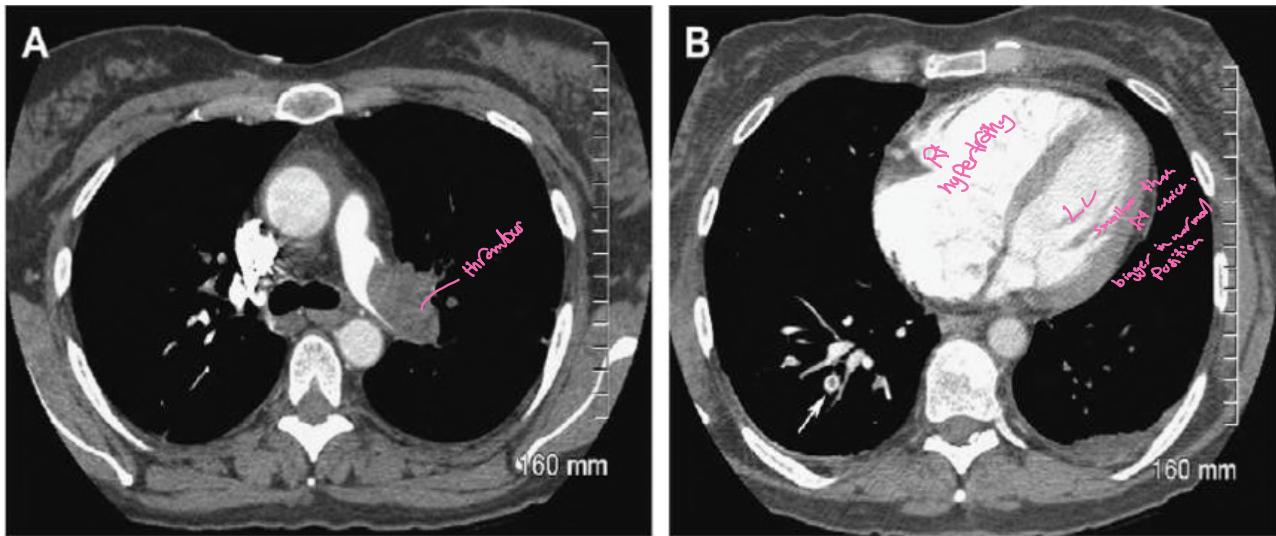

Two axial CT scans of the chest:

- A) Shows acute pulmonary embolism (PE) in the left main pulmonary artery (LMA) as a complete filling defect

- B) Shows right ventricle (RV) and right atrium (RA) moderately dilated, with central partial filling defect of acute PE (arrow) in right lower lobe posterobasal segmental artery (Polo mint sign)